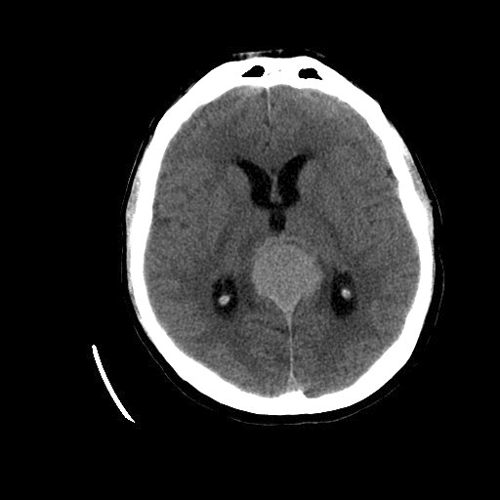

Imaging of the Case: MRI demonstrated a 4.4 x 3.5 x 4.7 cm mass in the pineal region. The lesion is isointense on T1 with homogeneous post contrast enhancement (Panel A) and slightly hyperintense on T2. The tumor is relatively well demarcated. The tectal plate is not visualized and mass effect is demonstrated upon the third ventricle outflow tract and midbrain. A second but smaller lesion of similar imaging characteristic is dmonstrated in the suprasellar region involving the optic chiasma. There is also mild hydrocephalus. CT scan (Panel B) demonstrated also a similar enhancing lesion. Calcifications are demonstrated on both MRI and CT scan.